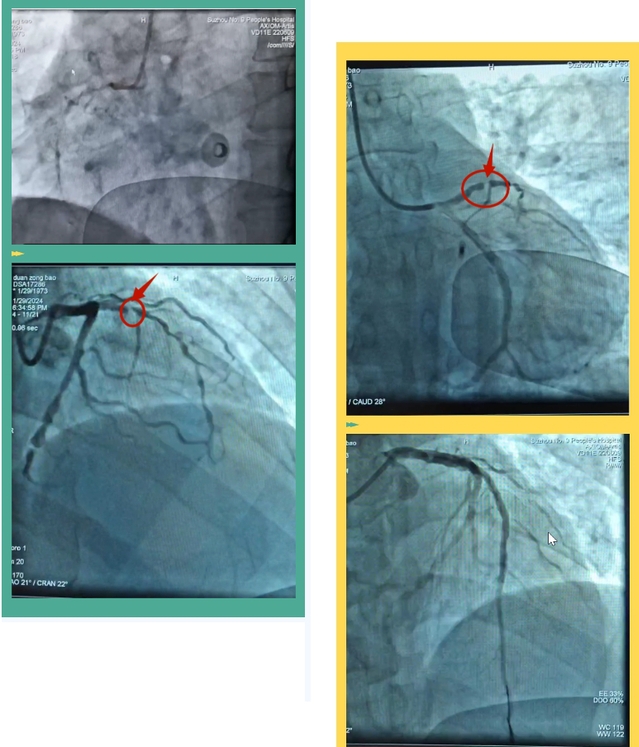

早已做好急诊介入准备的心血管内科介入团队殷人麟副主任医师、沈峻主治医师、沈道文护师,成功完成了PCI术。这位高危前壁心肌梗死且心电图体现墓碑样改变的急重症患者,供应心脏的三根冠脉均成严重狭窄,雪上加霜的是最重要的前降支出现了完全闭塞。手术顺利,借助于第一时间准备的主动脉球囊反搏(IABP)生命支持设备,患者术中血压及心率均控制在良好范围,术后恢复好,第二天就撤离了IABP生命支持设备,逐步康复,平稳出院。